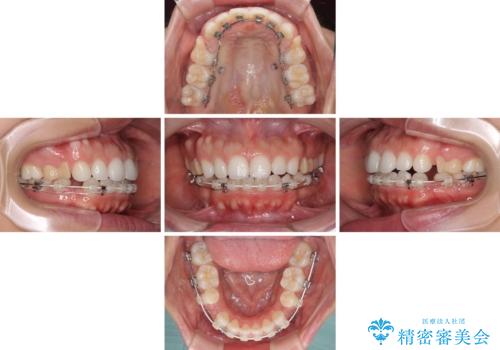

- 矯正装置

- ハーフリンガル

- 2年9ヶ月

- 10-30回